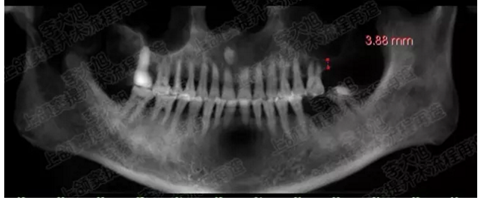

病例二

剩余骨量2mm

003.png

提升10mm

004.png